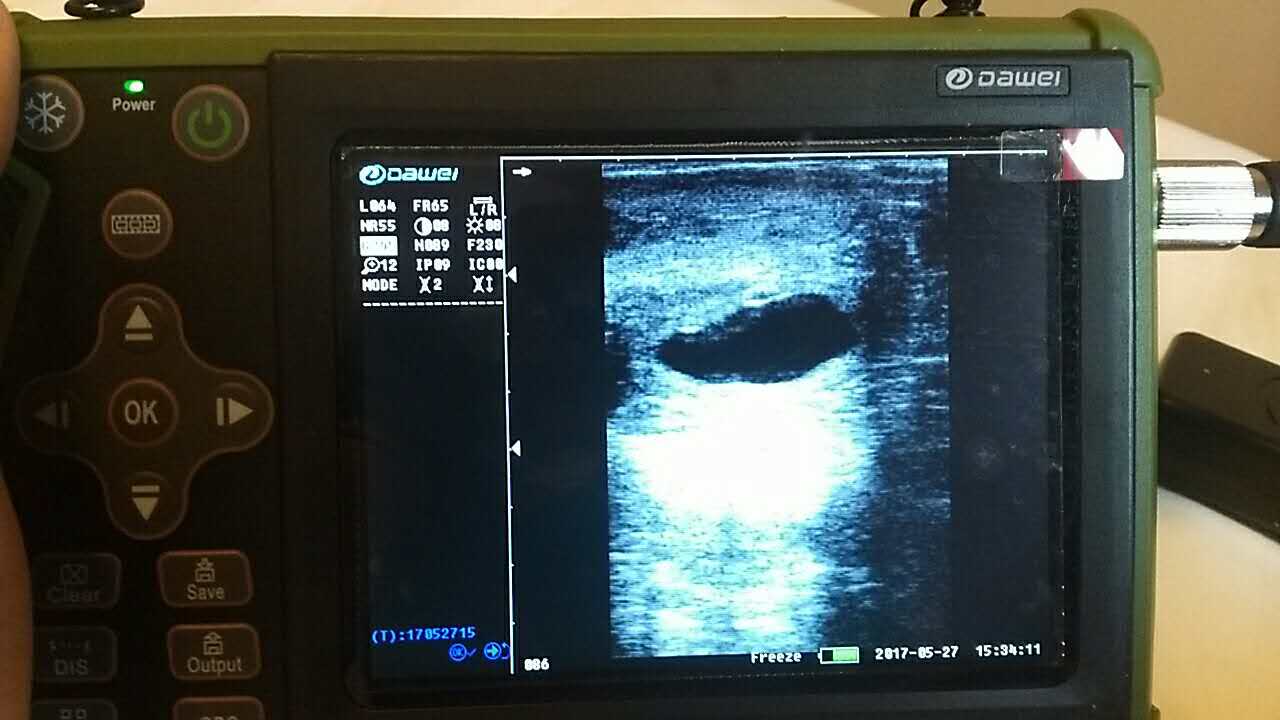

圖像“凍結(jié)”,操作鍵不好用。